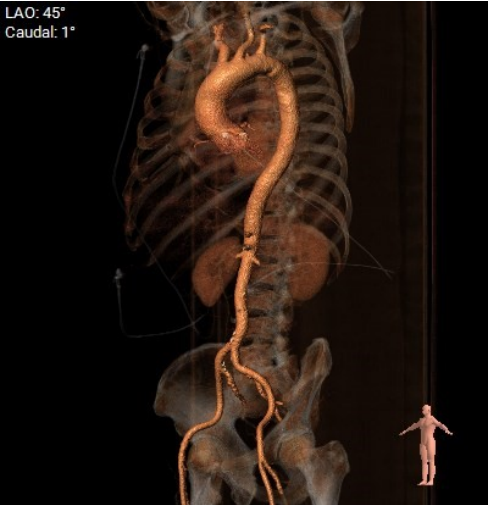

CT分析:

术前CT分析判断该心耳为反鸡翅型左心耳,选择偏下略偏前的位置进行房间隔穿刺。在工作体位造影后,可见左心耳内梳状肌发达,反鸡翅叶显影清晰,鞘管轴向佳。经DSA测量左心耳开口18mm深度17mm,结合TEE测量数据,综合考虑选用WATCHMAN24mm封堵器进行封堵。在展开封堵器时利用在体内借深度技巧,保证封堵器封堵位置合理。封堵器展开后经造影检查封堵器封堵效果理想,牵拉试验稳定。超声评估封堵器各角度无残余分流,位置理想,满足PASS原则,随即释放封堵器,一站式手术顺利结束。